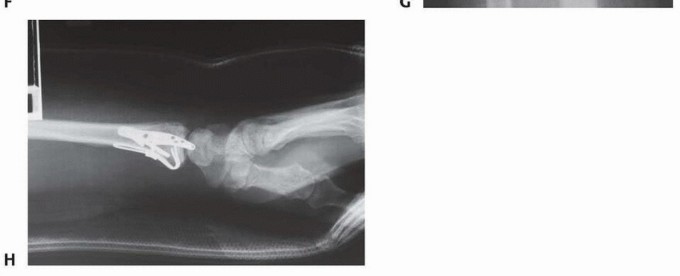

TECH FIG 6 • Volar rim fixation with a volar buttress pin. A,B. Articular fracture with axial instability pattern of volar rim. C. Insertion of Kirschner wires. D. Cutting and inserting legs. E. Reduction of teardro (continued) 85

TECH FIG 6 • (continued) F. Completed fixation. G,H. Volar buttress pin fixation to control rotational alignment of volar rim fragment. Fine-tune the reduction and fix it proximally with a minimum of two screws and washers ( TECH FIG 6F-H). If needed, a blocking screw can be placed just proximal to the end of the buttress pin to prevent shortening of the fragment. Alternatively, a wire plate can be used to secure the implant proximally. Volar Hook Plate Fixation Volar hook plates are useful alternative to volar buttress pins for fixation of unstable volar rim fragments, particularly for small distal fragments associated with axial instability patterns of the volar rim or volar instability patterns associated with volar shear fractures. Expose and reduce the volar rim fragment according to the technique described for the volar buttress pin. If possible, provisionally hold the reduction with a Kirschner wire in the radial and ulnar border. Position and insert a 0.045-inch Kirschner guidewire distally down the center of the teardrop along the intended path of the hooks of the plate. Confirm the position with the C-arm. For hard bone, place a volar hook plate drill guide over the guidewire, and predrill the cortex for insertion of the hooks. In osteoporotic bone, this step may not be necessary. Insert the volar hook plate over the guide pin and seat into the distal fragment ( TECH FIG 7A-C). Place a distal locking peg of appropriate length after predrilling with a fixed-angle peg guide. Fix the plate proximally with standard bone screws.